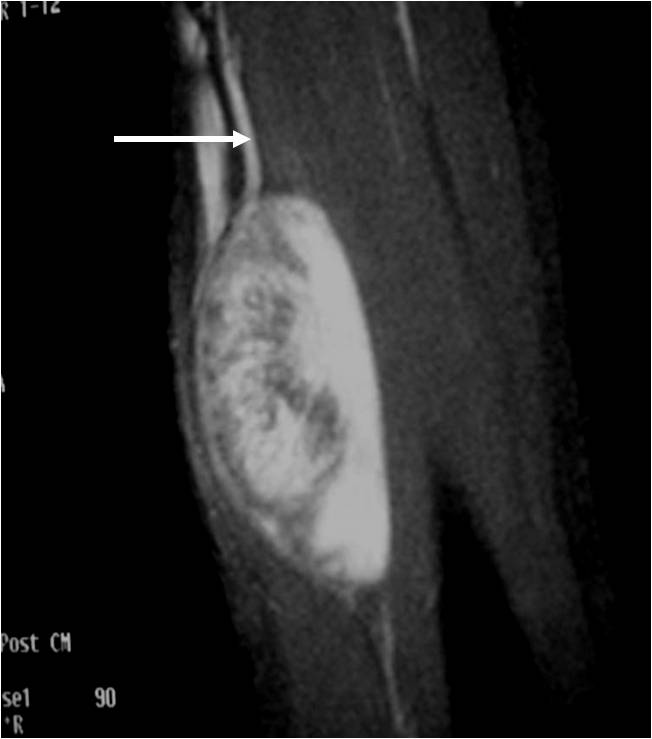

• Nerve: Tubular structure visualized entering and exiting the mass (may be difficult to see with small lesions or lesions of the trunk or retroperitoneum) (Fig. 2 & 4)

Fig. 1-4 MR image demonstrates a 5 cm intermuscular mass in the anterior compartment of the arm arising along the course of the neurovascular structures. Isointense to muscle on T1W image and heterogeneous high signal on T2W with low signal in the central area (Antoni A) and peripheral high signal (Antoni B), known as “Target Sign”. Coronal image shows a structure entering and exiting the mass (median nerve).